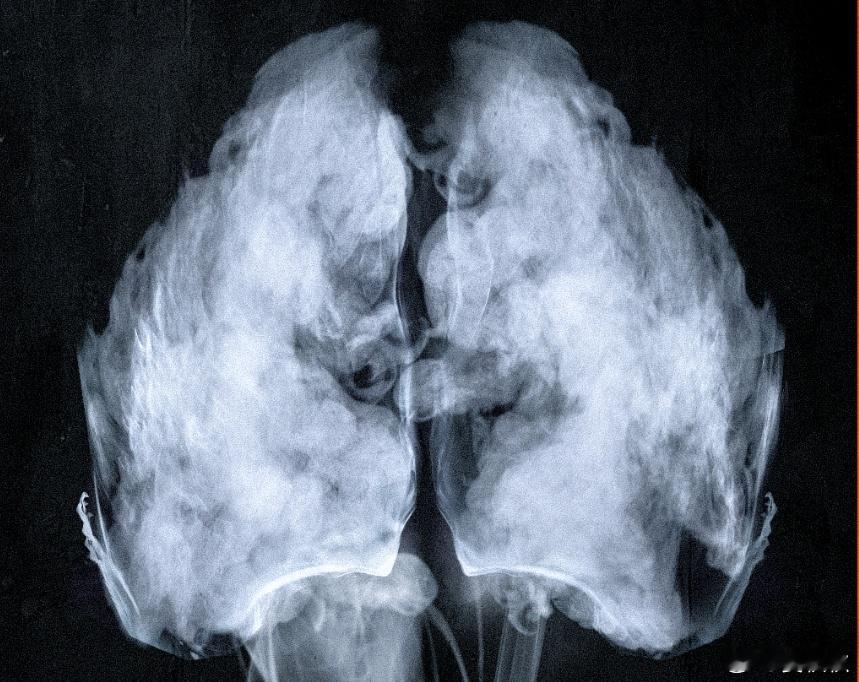

13岁的女孩患上胃癌晚期,医生的诊断是,二手烟所致。这件事情,发生在河南省肿瘤医院。医生说,女孩的父亲常年吸烟,且在家中从未避开孩子,导致孩子从小生活在烟雾缭绕的环境里。为女孩进行手术时,发现情况远比预想的更糟——腹腔打开后,又无奈地将其合上。因为肿瘤已经全身多发转移,腹腔内“像撒豆子一样”布满了大小不一的肿瘤,根本无法手术。医生表示,“这种是没有任何治愈机会的。”一个花季少女的生命,因为长期暴露在二手烟中,被推向了无法挽回的境地。这样的一起悲剧,再次敲响了警钟:一手烟和二手烟的危害是相同的。只要吸入,烟草烟雾中的致癌物就会对全身造成伤害,尤其是对呼吸系统尚未发育完全的儿童。吸烟有害健康。如果因为经济利益、社会治理、历史遗留问题,而不得不生产香烟的话。那么“二手烟”就应该完全制止。烟民在家中肆无忌惮地吸烟,忽视了对家人、尤其是孩子健康的侵害。这更是不可忍受。必须牢记,二手烟是没有“安全剂量”的,任何暴露都可能带来风险。13岁女生吸13年二手烟确诊胃癌晚期爸爸在家吸烟13岁女儿腹腔长满肿瘤一人吸烟全家面临癌症威胁晏秋秋